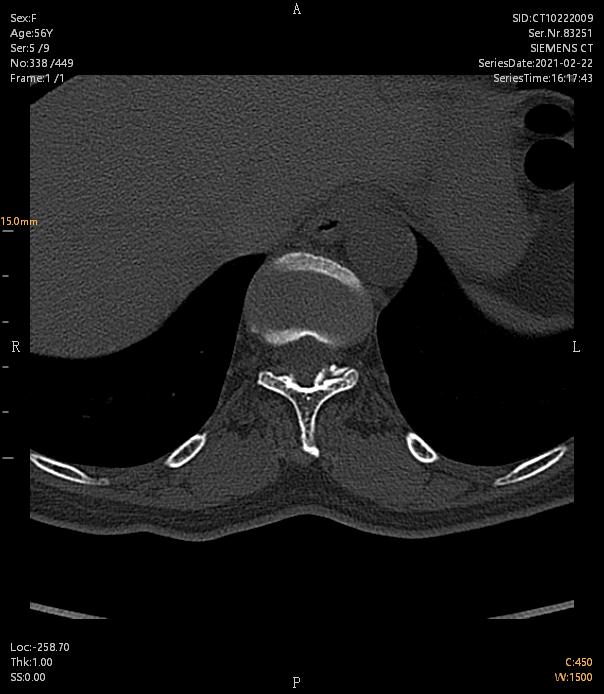

术前ct

术后ct

(患者术前双下肢后侧疼痛,麻木1年,行走,平卧加重。查体:双侧胸11以下浅感觉减退,病理反射未引出,术后症状完全消失)